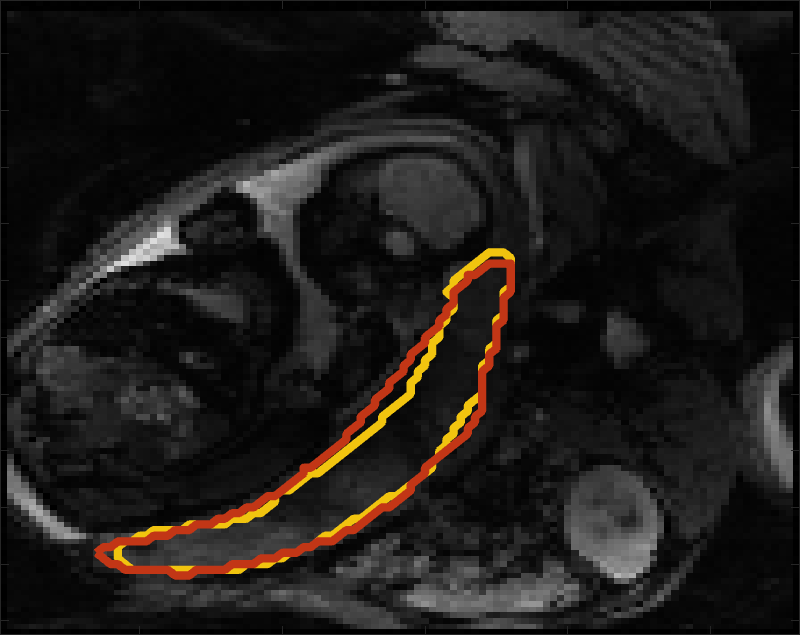

Despite its importance for many downstream clinical research tasks, placental segmentation is often performed manually and can take a significant amount of time, even for a trained expert. For BOLD MRI studies, manual segmentation is rendered more challenging due to the sheer number of MRI scans acquired and rapid signal changes due to the experimental design. Experiments acquire several hundred whole-uterus MRI scans to observe signal changes in three stages: i) normoxic (baseline), ii) hyperoxic, and iii) return to normoxic. During the hyperoxic stage, the BOLD signals increase rapidly, leading to hyperintensity throughout the placenta. Furthermore, the placental shape can undergo large deformation caused by maternal breathing, contractions, and fetal motion which can be particularly increased during hyperoxia [25]. See Fig. 1 for two examples.

Fig 3 compares the predicted label maps with ground truth on subjects with increasing Dice scores using the BW-CE model. The model accurately identifies the location of the placenta, but in the worst cases misses boundary details.